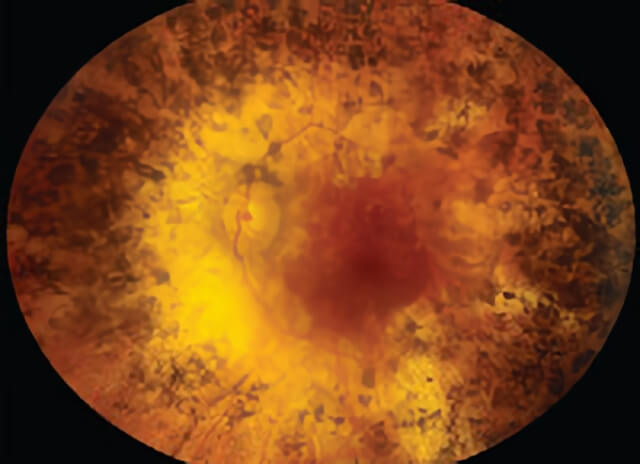

Retinitis Pigmentosa is shown in this photograph.

Color montage photo of a patient with retinitis pigmentosa.